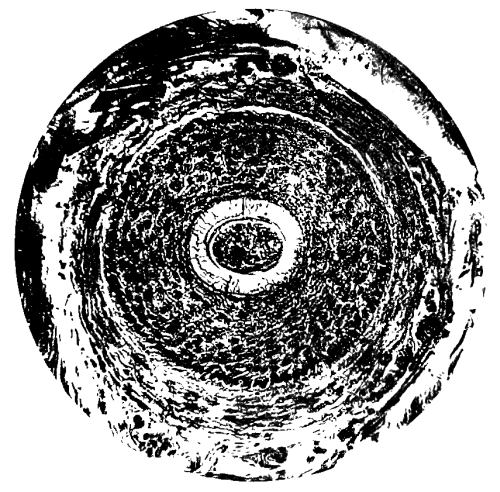

Plate showing Centre of Ossification in the Lower Epiphysi of PAGE

Femur in full time Fœtus To face 64

A plate, showing the centre of ossification in the lower epiphysis of the femur in a full time fœtus, has been introduced at the last moment, and will be found opposite page 64. References to the subject may also be found on pages 33 and 174.